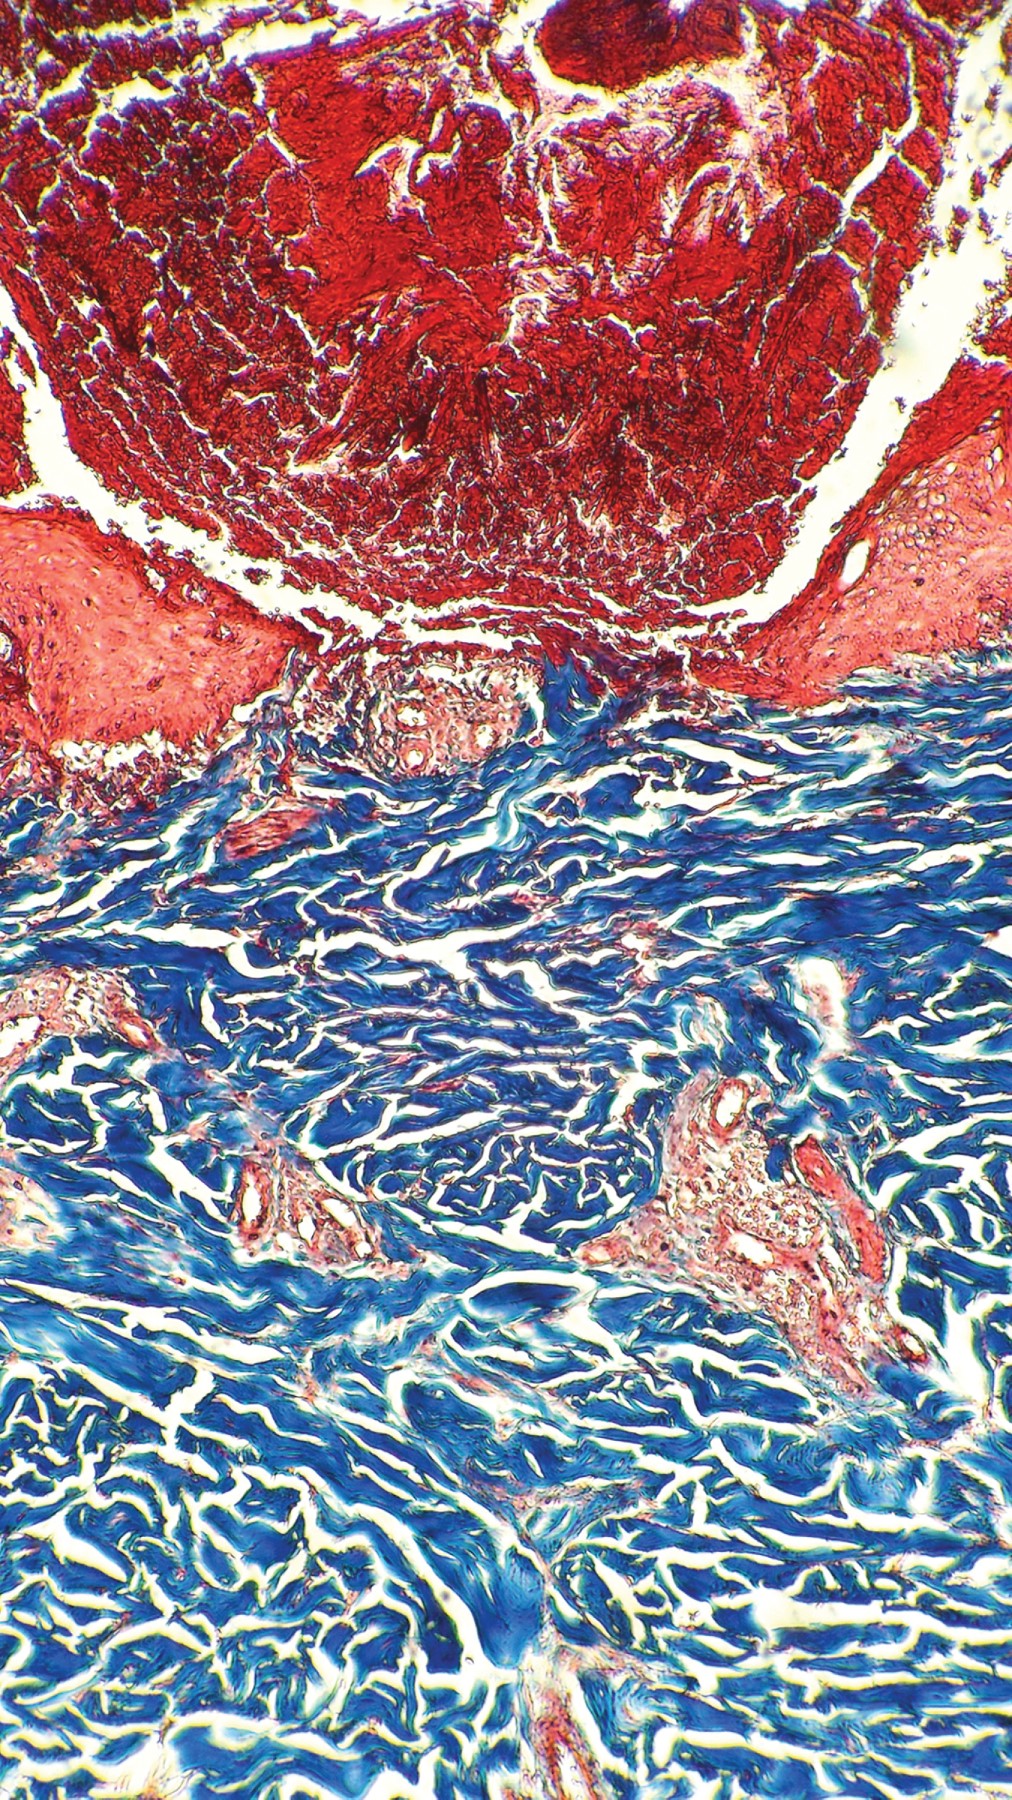

Acquired reactive perforating collagenosis

Perforating dermatoses are a group of diseases clinically characterized by transepidermal shedding of various skin materials. Four primary classical forms have been described in which the removal material represents the distinctive clinical picture. In secondary cases, the perforation and elimination of the fibers of the connective tissue constitute a phenomenon that accompanies other dermatoses. Acquired reactive perforating collagenosis belongs to the latter group. The etiology is not clear. It is associated with metabolic disorders and certain neoplasms. Pruritus is considered a key pathogenic factor, since constant scratching generates microtrauma in genetically predisposed patients, causing focal degeneration of collagen fibers. The most frequent topography is in the trunk (77%) and the extremities (64%), of which the extensor areas are involved. It manifests clinically with the presence of erythematous papules with an umbilicus appearance, with a firmly adhered keratin plug in the center. Histopathology shows transepidermal removal of collagen fibers. Because the treatment is not yet well standardized, the management of pruritus is considered one of the bases of it. It is recommended to treat the associated diseases.

Figure 1